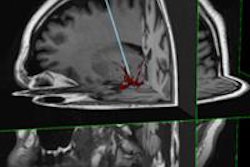

MRI Interventions announced that the neurological surgical team at University of Kansas Medical Center performed the first stereotactic laser ablation of the hippocampus using the company's ClearPoint Neuro navigation system.

The procedure occurred on a 22-year-old presenting with medically intractable seizures, which have since stopped.

The ClearPoint system enables minimally invasive neurosurgery under continuous MRI guidance, according to the company.